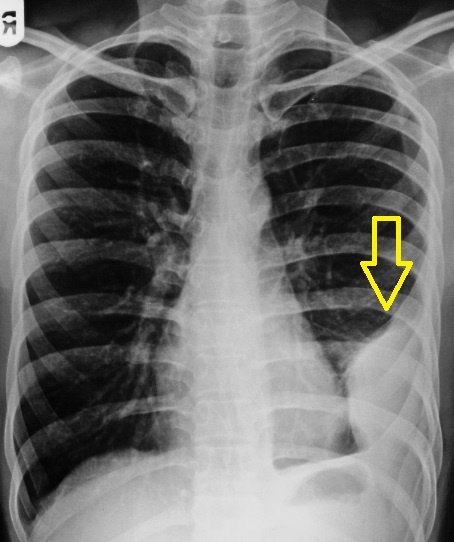

- Рентген/КТ грудной клетки — выявление уровня жидкости.

Плеврит – это воспаление плевры (серозной оболочки, покрывающей легкие и выстилающей грудную полость), которое может сопровождаться накоплением жидкости (экссудативный плеврит) или протекать без выпота (сухой плеврит)